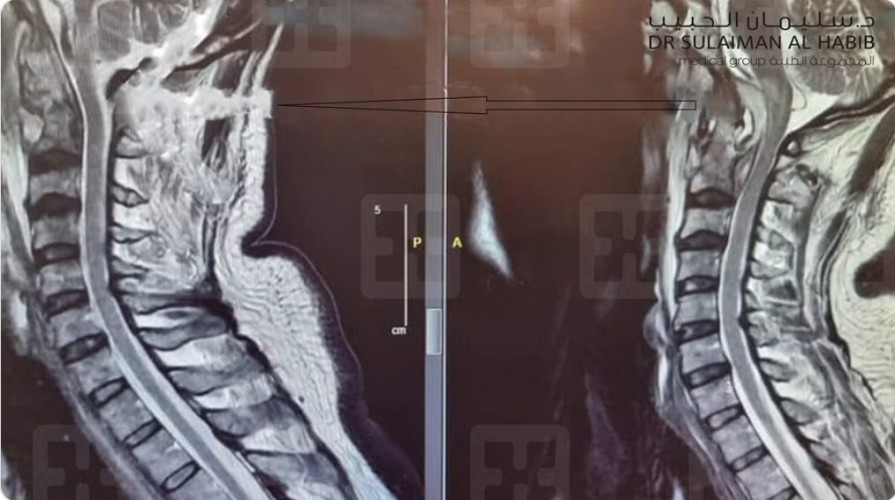

وقال د. ناجي مسعود استشاري جراحة المخ والأعصاب والعمود الفقري، رئيس الفريق الطبي المعالج: إن العملية التي أجريت للمريض تُعد الأولى من نوعها في المملكة، ولم تُجرَ منذ العام 1920م سوى “36” مرة على مستوى العالم؛ مضيفًا أن المريض سعودي الجنسية، وأُدخِل المستشفى عن طريق الطوارئ، وهو يعاني من شلل كامل للشق الأيسر من الجسم، وضَعف في التنفس، وحالة دوار مستمرة، وأُخضع لحزمة من الفحوصات الطبية الدقيقة؛ من أهمها الأشعة المقطعية CT- Scan والرنين المغناطيسي MRI، وبيّنت الصور والتحاليل وجود كتلة صديدية كبيرة الحجم جزء منه سائل والآخر صلب، وتُسبب ضغطًا شديدًا على أكثر من منطقة حساسة؛ مما نتج عنه الأعراض الحادة التي عانى منها المريض.

وأضاف د.مسعود أن الفريق الطبي أخضع الحالة لدراسة عميقة، وخلُص إلى خطة علاجية مكونة من مرحلتين، وبعد إكمال الترتيبات اللازمة أُخضع المريض في المرحلة الأولى لعملية دقيقة ومعقدة، تم الدخول فيها عبر الفم؛ حيث تم رفع اللهاة وفتح الطريق إلى الجدار الخلفي للبلعوم، والوصول عبره إلى الفقرة الأولى، ومن ثم إلى الفقرة الثانية التي بها الصديد والالتهاب الشديد، وتمت إزالة الكتلة بالكامل، وتحرير عنق الدماغ والنخاع الشوكي من الضغط، فعادا إلى وضعهما الطبيعي، وتكللت العملية التي استمرت لنحو “6” ساعات -ولله الحمد- بالنجاح التام، ونُقل المريض إلى العناية المركزة؛ حيث بقي فيها تحت التنفس الاصطناعي حتى موعد العملية الثانية، التي جرت بعد “5” أيام، وتم فيها تثبيت الفقرتين الأولى والثانية، ثم أعيد إلى العناية المركزة، وبدأت حالته الصحية في التحسن بنسق متسارع؛ حيث رُفِعَ عنه جهاز التنفس الاصطناعي بعد “72” ساعة من العملية الثانية، وبدأ يحرك أطراف شقه الأيسر الذي كان مصابًا بالشلل التام، وفي اليوم السادس نُقل إلى غرفة تنويم اعتيادية، وبدأ يمشي بمساعدة “المشاية”، وبعد نحو أسبوعين خرج من المستشفى على قدميه وسط فرحة كبيرة من أهله، والآن عاد إلى عمله وممارسة حياته اليومية بصورة طبيعة.